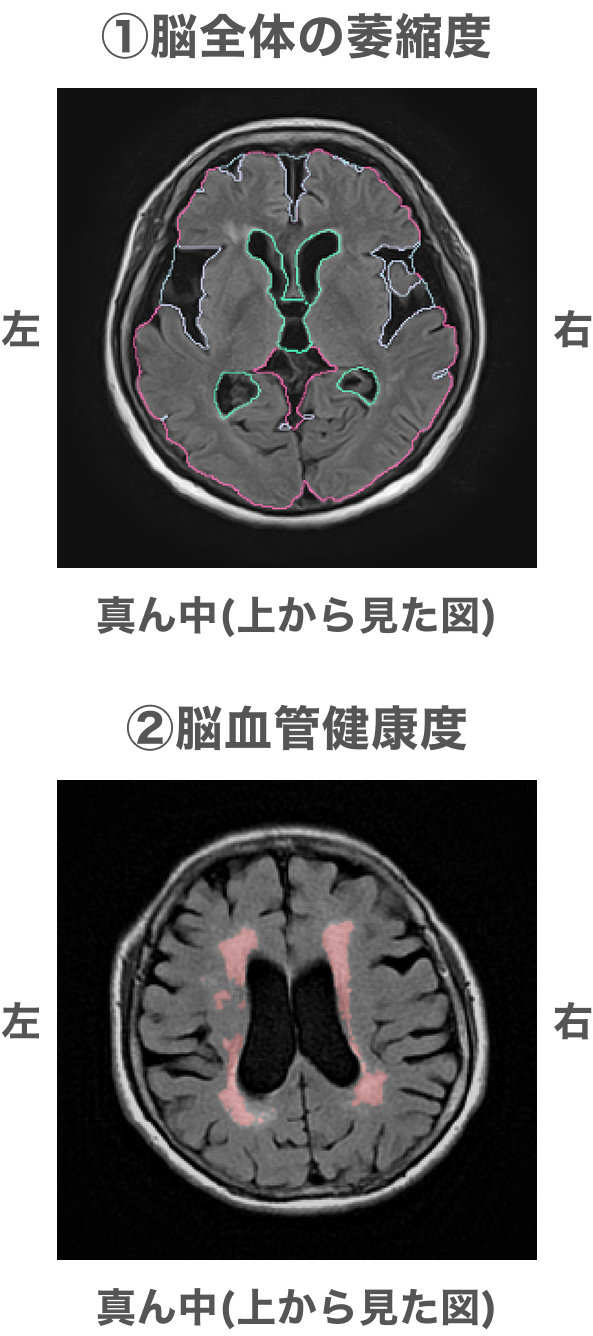

「MVision health」は株式会社エムが過去3万件以上のビッグデータを元に開発したAIによる画像解析レポートです。脳の萎縮の程度と脳血管の健康度(白質病変の量)を数値化することで、同年代の健康な脳と比較した進行の程度や、経年で見たときの進行のスピードを確かめることができます。